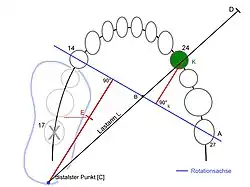

Der Belastungswert der zu ersetzenden Zähne muss nach Vest dem Belastungswert der Pfeilerzähne entsprechen, also mindestens gleich oder größer als dieser sein, um eine ausreichende Langzeitprognose einer anzufertigenden Brücke zu gewährleisten. Fehlen beispielsweise die unteren vier Frontzähne 32–42, die einen Belastungswert von 2 + 1 + 1 + 2 = 6 aufweisen, so genügen die beiden unteren Eckzähne 33 und 43, die einen Belastungswert von 5 + 5 = 10 aufweisen, als Pfeilerzähne zum Ersatz dieser Zähne. Fehlen jedoch die beiden Molaren 26 und 27 (Belastungswert 6 + 6 = 12), so genügen nach Vest die beiden endständigen Zähne 25 und 28 als alleinige Pfeilerzähne nicht (Belastungswert 4 + 4 = 8). Es sollte deshalb der Zahn 24 in einen Brückenzahnersatz mit einbezogen werden (Belastungswert 4 + 4 + 4 = 12).

Kippungsgrad

Gekippte Zähne sind nicht so belastbar wie gerade stehende Zähne. Die Sharpey-Fasern, an denen der Zahn in der Alveole (Zahnfach) aufgehängt ist, werden bei Belastung ungleichmäßig gedehnt und belastet. Durch eine Kippung können Schmutznischen entstehen, die zu Entzündungen führen können. Bei zu starker Kippung ist eine gemeinsame Einschubrichtung für den Zahnersatz schwer zu präparieren. Sie kann durch ein Ausgleichsgeschiebe überwunden werden. Alternativ kann der Zahn durch eine kieferorthopädische Behandlung wieder aufgerichtet werden. Eine Kippung von bis zu 30° ist tolerabel. Eine größere Kippung schränkt die Verwendbarkeit stark ein. Falls keine weiteren wertigkeitsmindernden Faktoren vorliegen, können solche Zähne als endständige Pfeilerzähne Verwendung finden. Zähne mit einem Kippungsgrad von mehr als 40° haben keine Verwertbarkeit als Pfeilerzähne.[4] Optisch kann ein gekippter Zahn durch eine Krone zwar scheinbar aufgerichtet werden, jedoch trifft die Belastung immer auf einen gekippten Zahn.

Bei der Planung einer Brücke oder einer Teilprothese ist die Statik zu ermitteln und welchen Kräften die Pfeilerzähne ausgesetzt sein werden. Die Pfeilerzähne sind dahingehend zu bewerten, ob sie den zu erwartenden Belastungen standhalten können, wobei eine fachgerechte Konstruktion vorausgesetzt wird.[34]